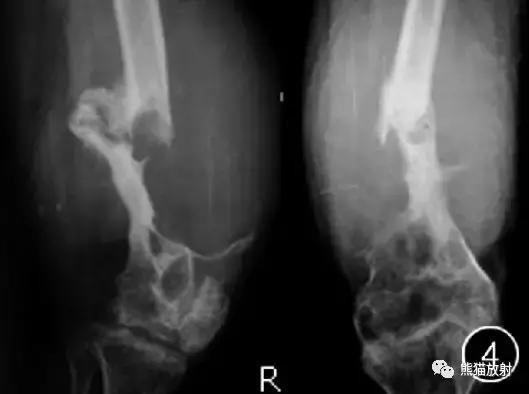

图4 男32岁。右侧股骨下段骨膜下型假肿瘤。DR显示右大腿下段软组织明显肿胀,股骨下段骨质膨胀并溶骨性破坏,边缘硬化,其内有残余骨嵴影,伴病理性骨折,骨折端见骨痂生长及骨质增生,左侧膝关节间隙变窄,关节面骨质硬化。